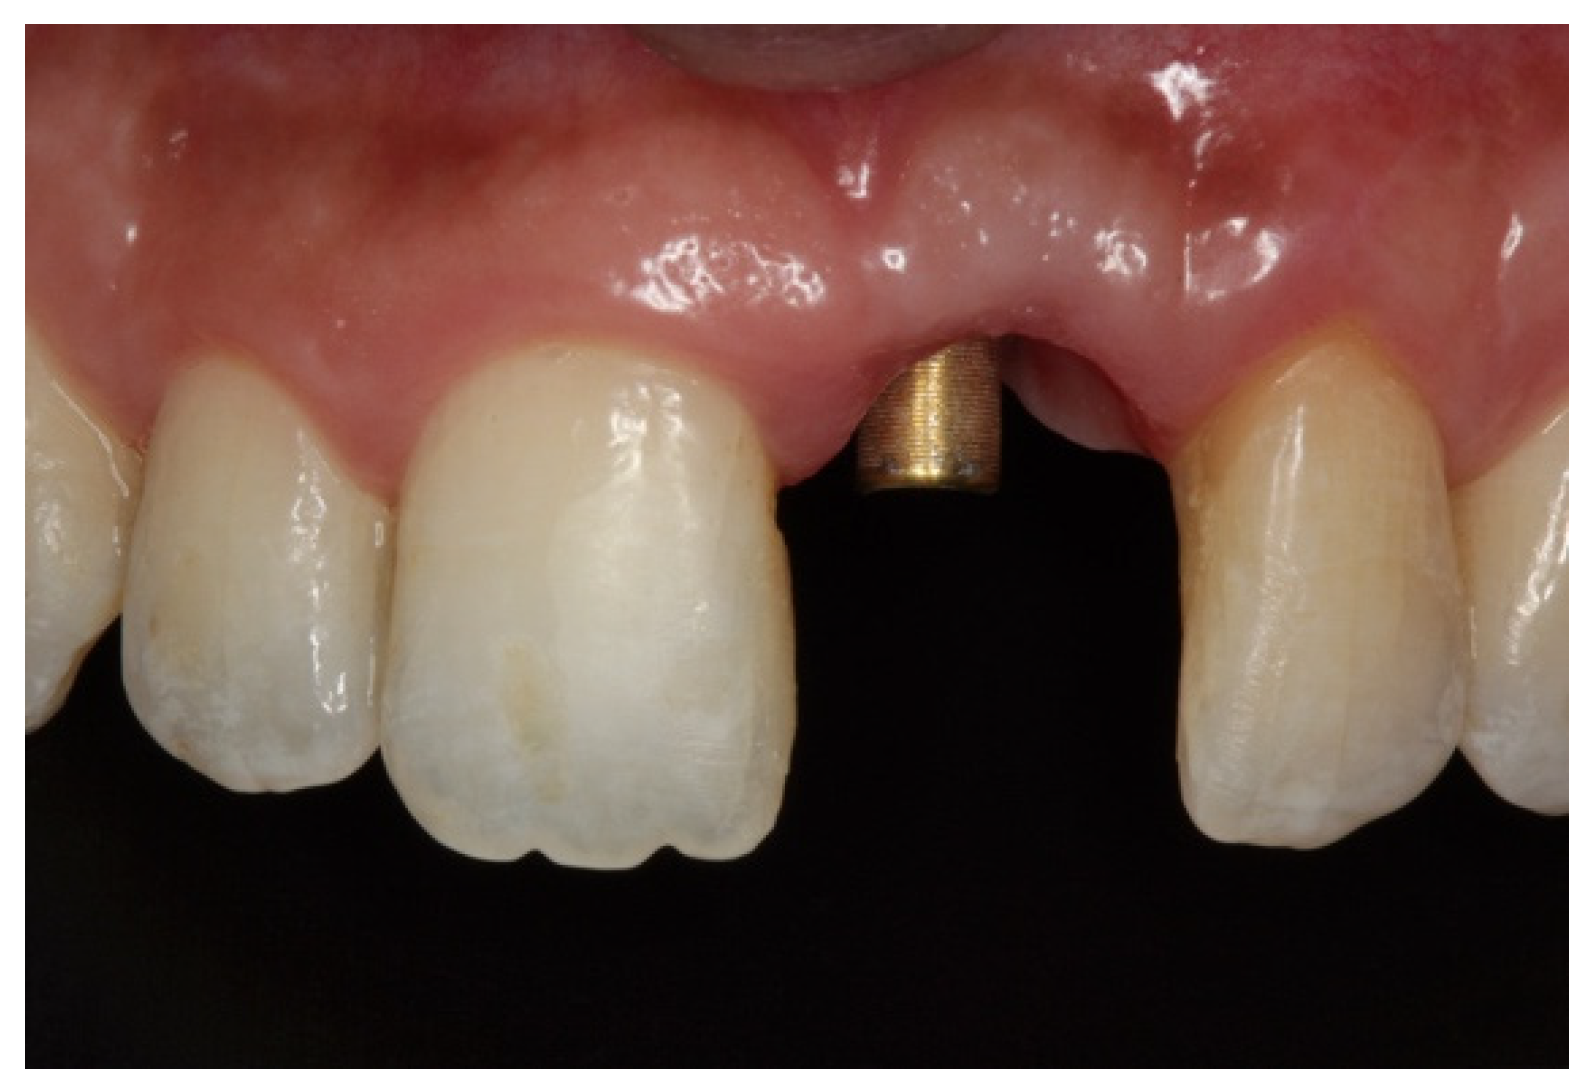

Figure 9.

(A–C) Placement of the porcelain crown.

Figure 10.

Radiographic control of Patient 1 at their 9-year follow-up. An occlusal view is shown on the left. (A) Sagittal view of the nasopalatine duct prior to treatment. (B) Post-treatment control radiograph: sagittal view of the implant in a three-dimensional position with the regenerated palatal wall.